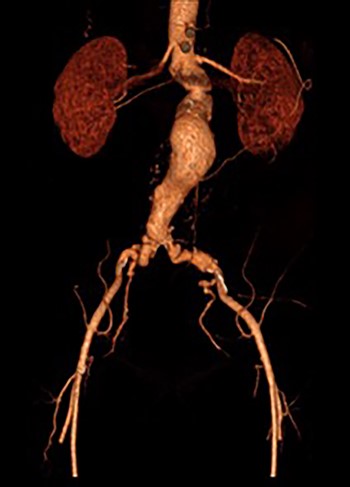

Post-lysis CT scanning showing fully re-canalized aorto-iliac system.

3D reconstruction CT scan, at 6-week interval from index procedure.

The patient was transferred to the high-dependency unit for observation during the thrombolysis. After 4-h, the patient was taken back to Interventional Radiology department for a check angiogram (Fig. 3). This demonstrated a fully re-canalized aorto-iliac system with no distal thrombotic or embolic complications. The thrombolysis infusion was stopped at this stage. In the post-operative period, anticoagulation has been continued with Apixaban. A CT scan 6 weeks post-procedure has confirmed ongoing patency of the endograft with no visible thrombus (Fig. 4).